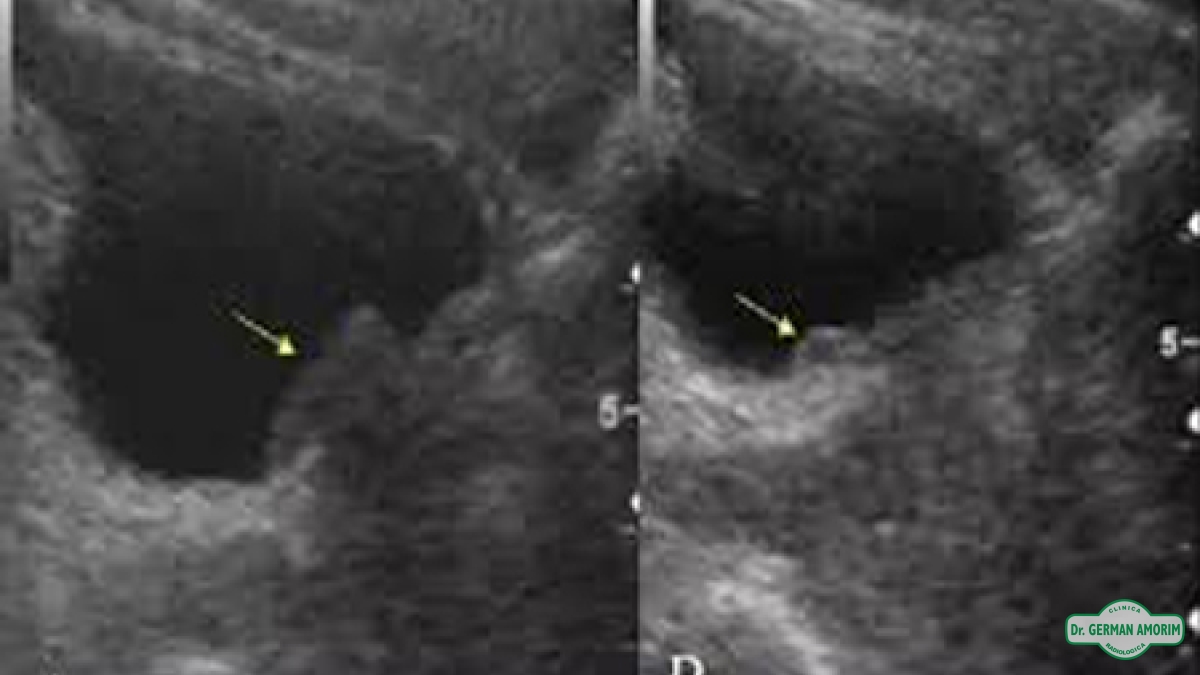

El ultrasonido de la próstata utiliza ondas sonoras para producir imágenes de la glándula prostática.

En este estudio se puede medir sus dimensiones, su peso, visualizar, deformaciones e irregularidad de las paredes.